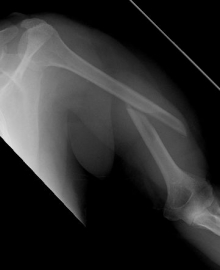

Picture: The subcapital humeral fracture shown here in the axis is not broken and only slightly bruised, so that a conservative therapy is possible. The left image shows the follow-up after 3 weeks. The patient has already started physiotherapy. The x-ray shows an increase bone healing.